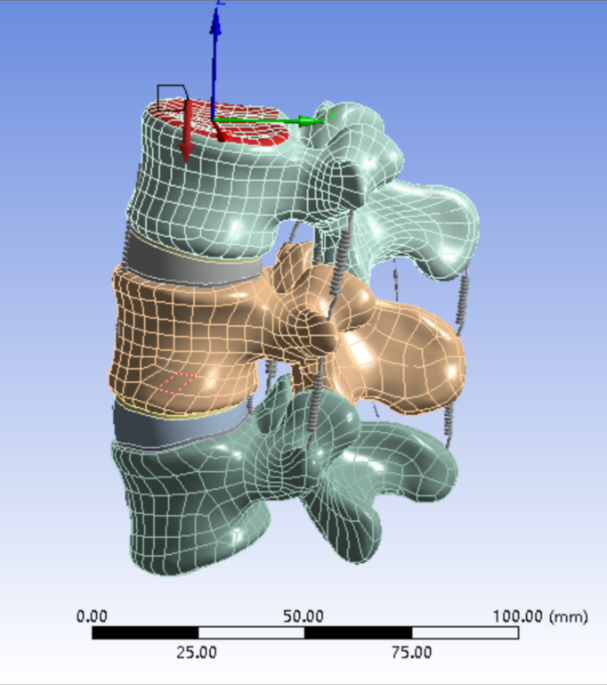

选取一名27岁青年男性志愿者在我院行腰椎螺旋CT扫描�����,扫描平面为���:第十二胸椎椎体至尾椎末端���,扫描厚度为0.625mm���,得到二维断层CT图像489张��,以DICOM格式进行储存���,导入计算机服务器�����。使用Mimics 19.0图像生成和编辑处理软件��,直接读取 DICOM格式的CT扫描数据进行三维重建���,见图 10����。根据软件中不同的灰度值来区分不同的组织����,用 Mimics 软件的阈值分割及区域增长功能画出腰椎(L3-5)����,不同的锥体用不同的颜色区分���,最后用图像填充功能填补图像中的空洞���,接着进行不同部位的三维重建��,得到仅包含骨性结构(L3-5)的模型��。将Mimics 软件得到的模型以STL格式模型文件导入Geomagic wrap2017软件中���,抹去模型钉状物和多余特征��,然后对模型进行优化光滑处理�����,将L3-5光滑处理后的每个锥体进行复制���,再将光滑后的模型在精确曲面中进行网格划分����,并进行构建曲面片及修理曲面片����,最后合成三维实体模型����,见图11�����。此时将复制的每个椎体模型外层向部件内部偏移2mm�����,内部充当松质骨��,外部的则定义为皮质骨����,椎弓根后部统一由皮质骨组成�����。随后将模型以STEP格式文件导入Solidworks2020软件中生成L3-5的实体模型零件��,并在模型零件中构建椎间盘��、髓核����、上下终板和软骨����,完成的实体模型���,此时的模型为单纯的正常腰椎三维几何模型���,各结构并未赋予材料属性与网格划分����,见图12�����。将模型导入ANSYS软件中���,随后对模型中皮质骨���、松质骨���、软骨����、终板���、纤维环���、髓核赋予相应的材料属性赋值���,尽可能地还原各组织材料的生理状况�����,提高模型的可靠性���。定义关节突关节面为 Frictional����,摩擦系数设为0.1��。在connections中建立spring模块���,模拟前纵韧带����、后纵韧带���、黄韧带��、棘间韧带���、棘后韧带���、横突间韧带及关节囊韧带��,各韧带对应刚度赋值��。建立完成后�����,对模型进行mesh操作构建网格���,见图13����。

图 12 Geomagic 图 13 ANSYS